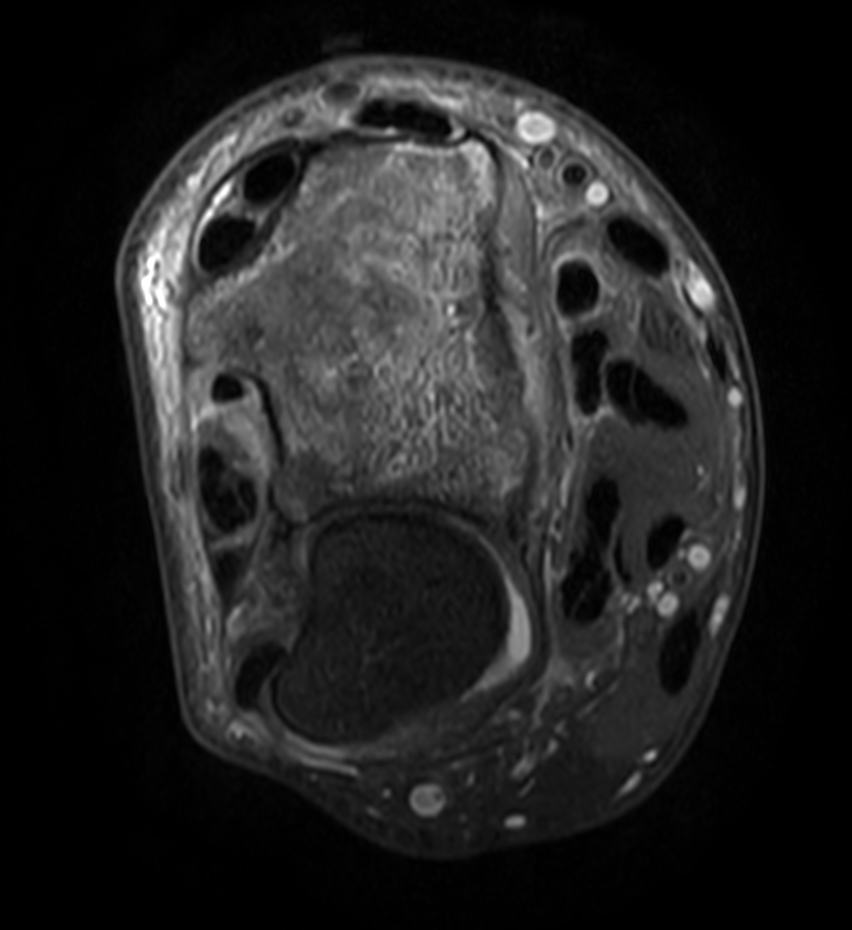

Patient with a wrist fracture. Compressed SENSE is used in all sequences, reducing the scan time while maintain equal image quality compared to scans without Compressed SENSE. 3D sequences have been added to this ExamCard with a comparable in-plane resolution but much thinner slices. Due to the shorter scan times that can be achieved thanks to Compressed SENSE, these 3D sequences could potentially replace the 2D sequences providing more confidence in making the diagnosis.

2D Axial PDw SPAIR

3D Axial PDw SPAIR